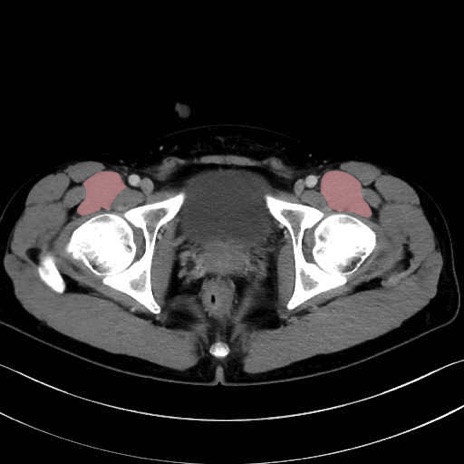

腸骨筋 (Iliacus)